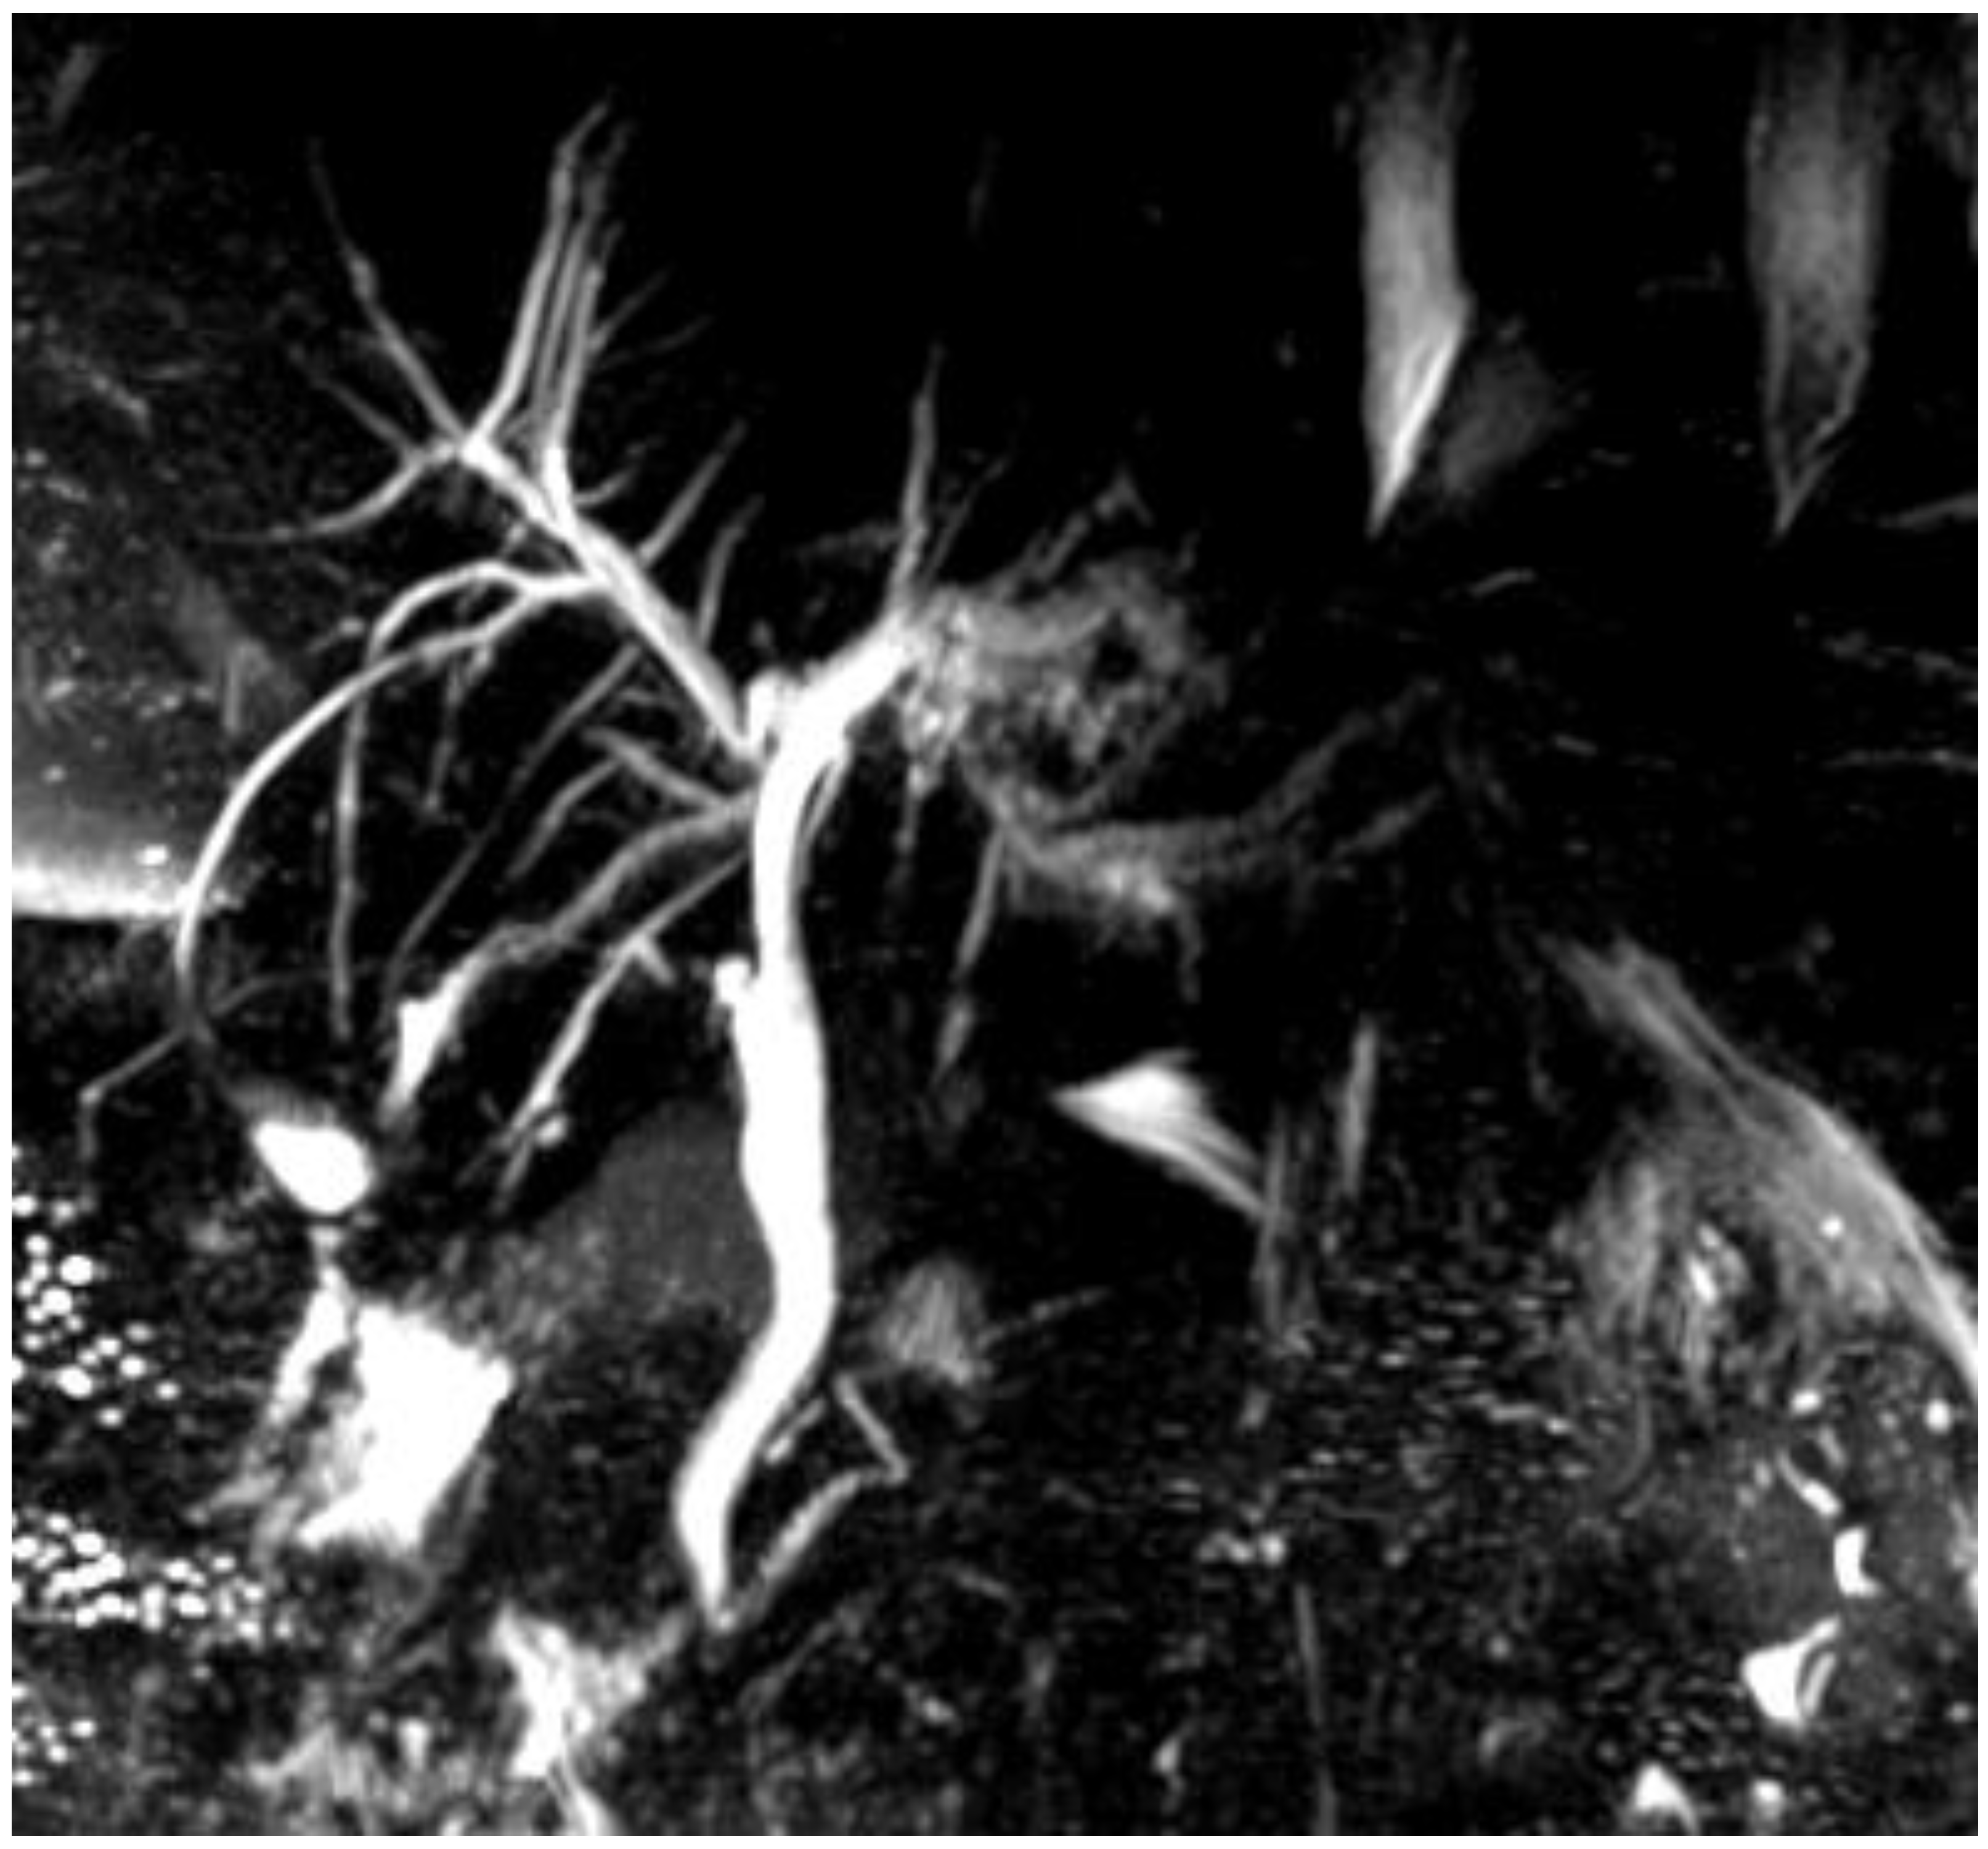

| Appropriate imaging modality and features | MRCP, ERC. Beaded appearance, pruned tree appearance, and band-like stricture. | MRCP. Diffuse or segmental narrowing of the intrahepatic and/or extrahepatic bile duct, associated with the thickening of the bile duct wall. | MRCP. Intraductal calculi and bile duct strictures. | CT-scan, MRI. The CT-scan: lesions with variable c.e., may present as hypovascular with delayed enhancement because of fibrosis. The MRI may produce hypointense on T1 sequences with moderate-to-high hyperintense on T2 sequences. | CT scan (scarce sensitivity for non-calcific stones) and MRCP. | CT scan, MRCP. MRCP most accurate, shows an extrinsic narrowing of the common hepatic duct, a gallstone in the cystic duct, dilation of the intrahepatic and common hepatic ducts, with a normal common bile duct. | CT scan and portal MR and MRCP. Show portal cavernoma, paracholedochal and/or epicholedochal dilations, portosystemic shunts and abnormal morphology of the bile duct. |